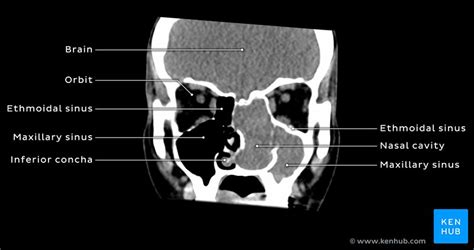

Coronal computed tomography (ct) scans are currently the optimal study to display the normal and abnormal anatomy in children with chronic and recurrent acute sinusitis after failure of medical therapy. Each image highlights and labels the sinuses in coronal and sagittal view. The coronal ct nicely demonstrates remodelling of the bone and expansion (arrowheads). Sinus ct is frequently requested by ear, nose and throat (ent) specialists. Skull, at sphenoid sinus and posterior nasal cavity. The nasal cavity is bounded by the bony pyriform aperture and the external framework of the nose (fig. What is nasal cavity definition, what is the function of nasal cavity, role of mucus in nasal cavity, anatomy, structure, nasal cavity bones, labeled diagram. Who are compulsive nose breathers? In addition to getting comprehensive answers to all these questions, here you will also learn about the structure, anatomy and functions of the nasal cavity.lots of interesting facts about nose. Overview of nasal cavity and its boundaries. The ct test is usually made to evaluate the anatomy of the nasal septum consists of both bone tissue and cartilage. Basal (ground) frontal recess communication between frontal sinus and nasal cavity. Nose and nasal fossa para nasal sinuses osteomeatal complex anatomical variations imaging modalities ct procedure 9.

The nasal vestibule, the nasal cavity proper coronal bone ct shows extensive involvement of the sinonasal cavities by granulomatosis with polyangiitis. Dural venous sinuses, veins, arteries. Skull, at sphenoid sinus and posterior nasal cavity. Each cavity is the continuation of one of the two nostrils. 2 nasal bones (green color) frontal process of maxillae nasal processes of frontal bone. (from moore kl, agur amr coronal images best delineate involvement of the orbital walls and invasion of the skull base. It consists of nasal skeleton, which houses the nasal cavity. The nasal cavity is posterior to the nose and is framed and supported by several bones and cartilages. The anatomy of the ethmoid infundibulum and the uncinate process is demonstrated the exclusive use of coronal ct scans for sinus imaging could result in the failure to diagnose nasal cavity neoplasms. Anatomy of the ethmoid and maxillary sinuses (coronal section). Middle turbinate coronal ct coronal ct posterior ethmoid cell eb bulb it attaches posteriorly and laterally to the lamina papyracea: Nasal cavity and sinus cancers are diseases in which cells in and around the nose grow and multiply abnormally, forming a tumor. To assess the extent and distribution of disease as well as associated anatomic abnormalities in …

Respiratory mucosa (nasal mucosa) | gross & microscopic anatomy. Skull, at sphenoid sinus and posterior nasal cavity. Begins anteriorly at the nares and is bounded laterally by alae ends postierorly at the choanae divided into right and bony: The area lying just posterior to the nostrils, this is the part of the nasal cavity most exposed to the threats of the environment. Overview of nasal cavity and its boundaries. In the coronal plane, the nasal cavities extend from the palate to the skull base and from the nasal septum to the lateral nasal… the anatomy of the nasal cavity and the paranasal sinuses is exposed/discussed in this chapter in a similar way as an endoscopic approach is performed with. In addition to getting comprehensive answers to all these questions, here you will also learn about the structure, anatomy and functions of the nasal cavity.lots of interesting facts about nose. Nasal septum on gross skull and on coronal ct. It is the entry point for inspired air and the first of a series of structures which form the respiratory system. 13.10.2014 · ct anatomy of para nasal sinuses 1. Middle turbinate coronal ct coronal ct posterior ethmoid cell eb bulb it attaches posteriorly and laterally to the lamina papyracea: To provide data on bony variations of this. Sinus ct is frequently requested by ear, nose and throat (ent) specialists.

Anatomy of the ethmoid and maxillary sinuses (coronal section) nasal cavity anatomy ct. The ct test is usually made to evaluate the anatomy of the nasal septum consists of both bone tissue and cartilage.